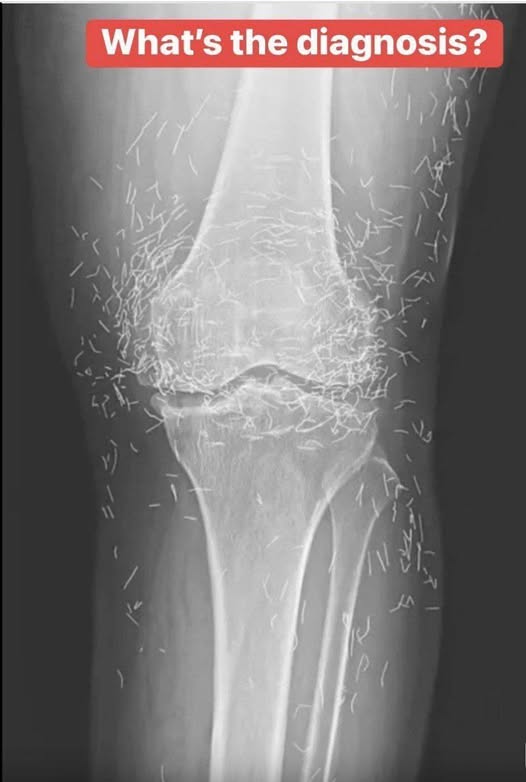

Years later, when doctors took X-rays to evaluate her knee condition, they weren’t prepared for what appeared on the images. Her knees were filled with dozens of bright, metallic flecks — tiny needles embedded deep within the joint area.

The findings were later documented in a case published by the New England Journal of Medicine.

Beyond inflammation, the needles created another problem: imaging complications. Metal objects can obscure parts of the anatomy on X-rays, making it harder for doctors to clearly assess joint damage or disease progression.

Even more concerning, the presence of metal inside the body can make certain scans dangerous. MRI machines rely on powerful magnetic fields, and embedded needles may shift during scanning, potentially damaging blood vessels or surrounding tissue. In short, future diagnostic options for this patient became limited.